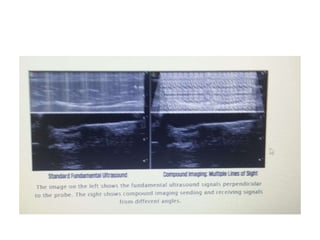

• Traditionally, transducers sendultrasound signals in a single “line of sight.” • This means it sends a sound signal perpendicular to the probe head, then listens for the echo. • With compound imaging, the ultrasound sends signals at multiple angles, allowing it to “see” tissue from multiple angles and eliminate artifact. • The following image best represents what’s really happening • Slide (42)

• Traditionally, transducers sendultrasound signals in a single “line of sight.” • This means it sends a sound signal perpendicular to the probe head, then listens for the echo. • With compound imaging, the ultrasound sends signals at multiple angles, allowing it to “see” tissue from multiple angles and eliminate artifact. • The following image best represents what’s really happening • Slide (23)